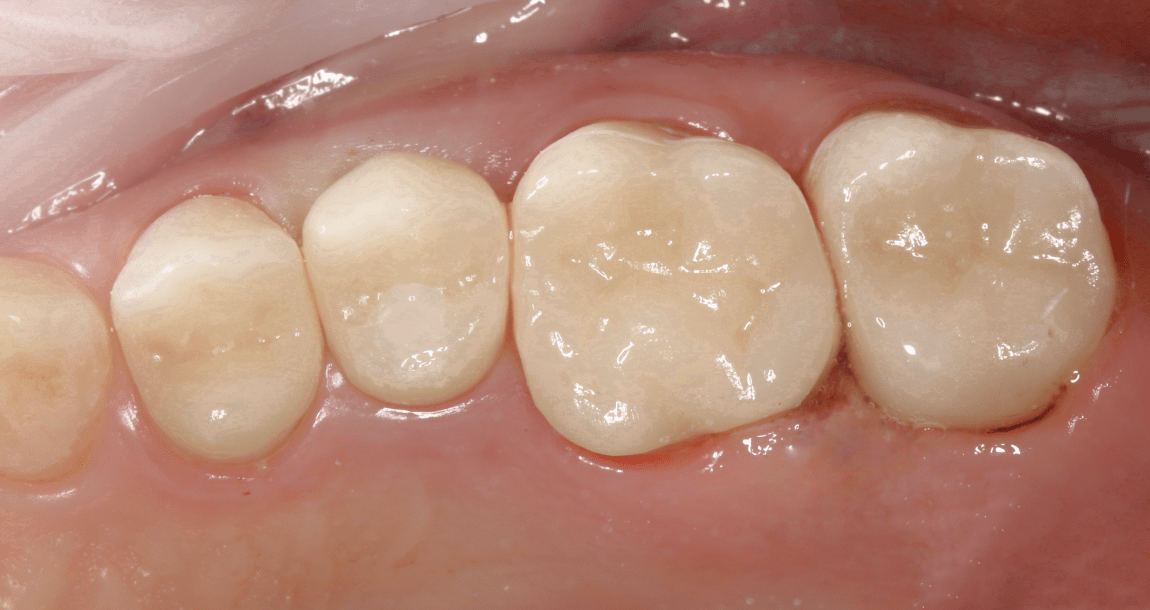

Имплантация — не «чрезмерная мера», а стандарт восстановления

Современные импланты восстанавливают:

- эстетику,

- функцию,

- нагрузку на кость,

- симметрию прикуса.

Это такой же нормальный метод лечения, как коронка или пломба — просто для более сложных случаев.